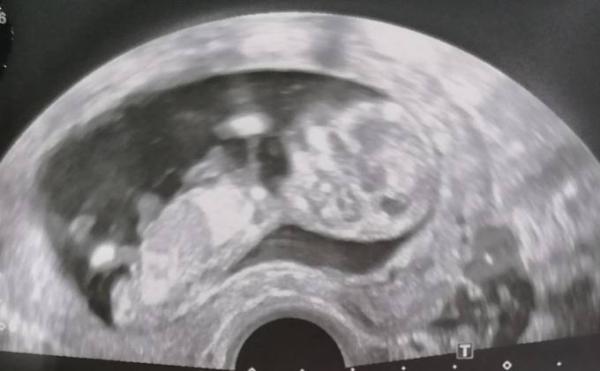

Seht ihr was? M/W

Was seht ihr?

Aus der Perspektive sieht man "nur" ein Baby, nicht ob M/W/D. Dafür der US von unten zwischen dem Beinen kommen.

Das ist echt schwierig zu sagen ...Ich würde tendenziell auf junge tippen ...Bei mir konnte man auch nichts sehen Ich gedulde mich nun bis zur 21/22 Woche .Oder es wird eine Überraschung